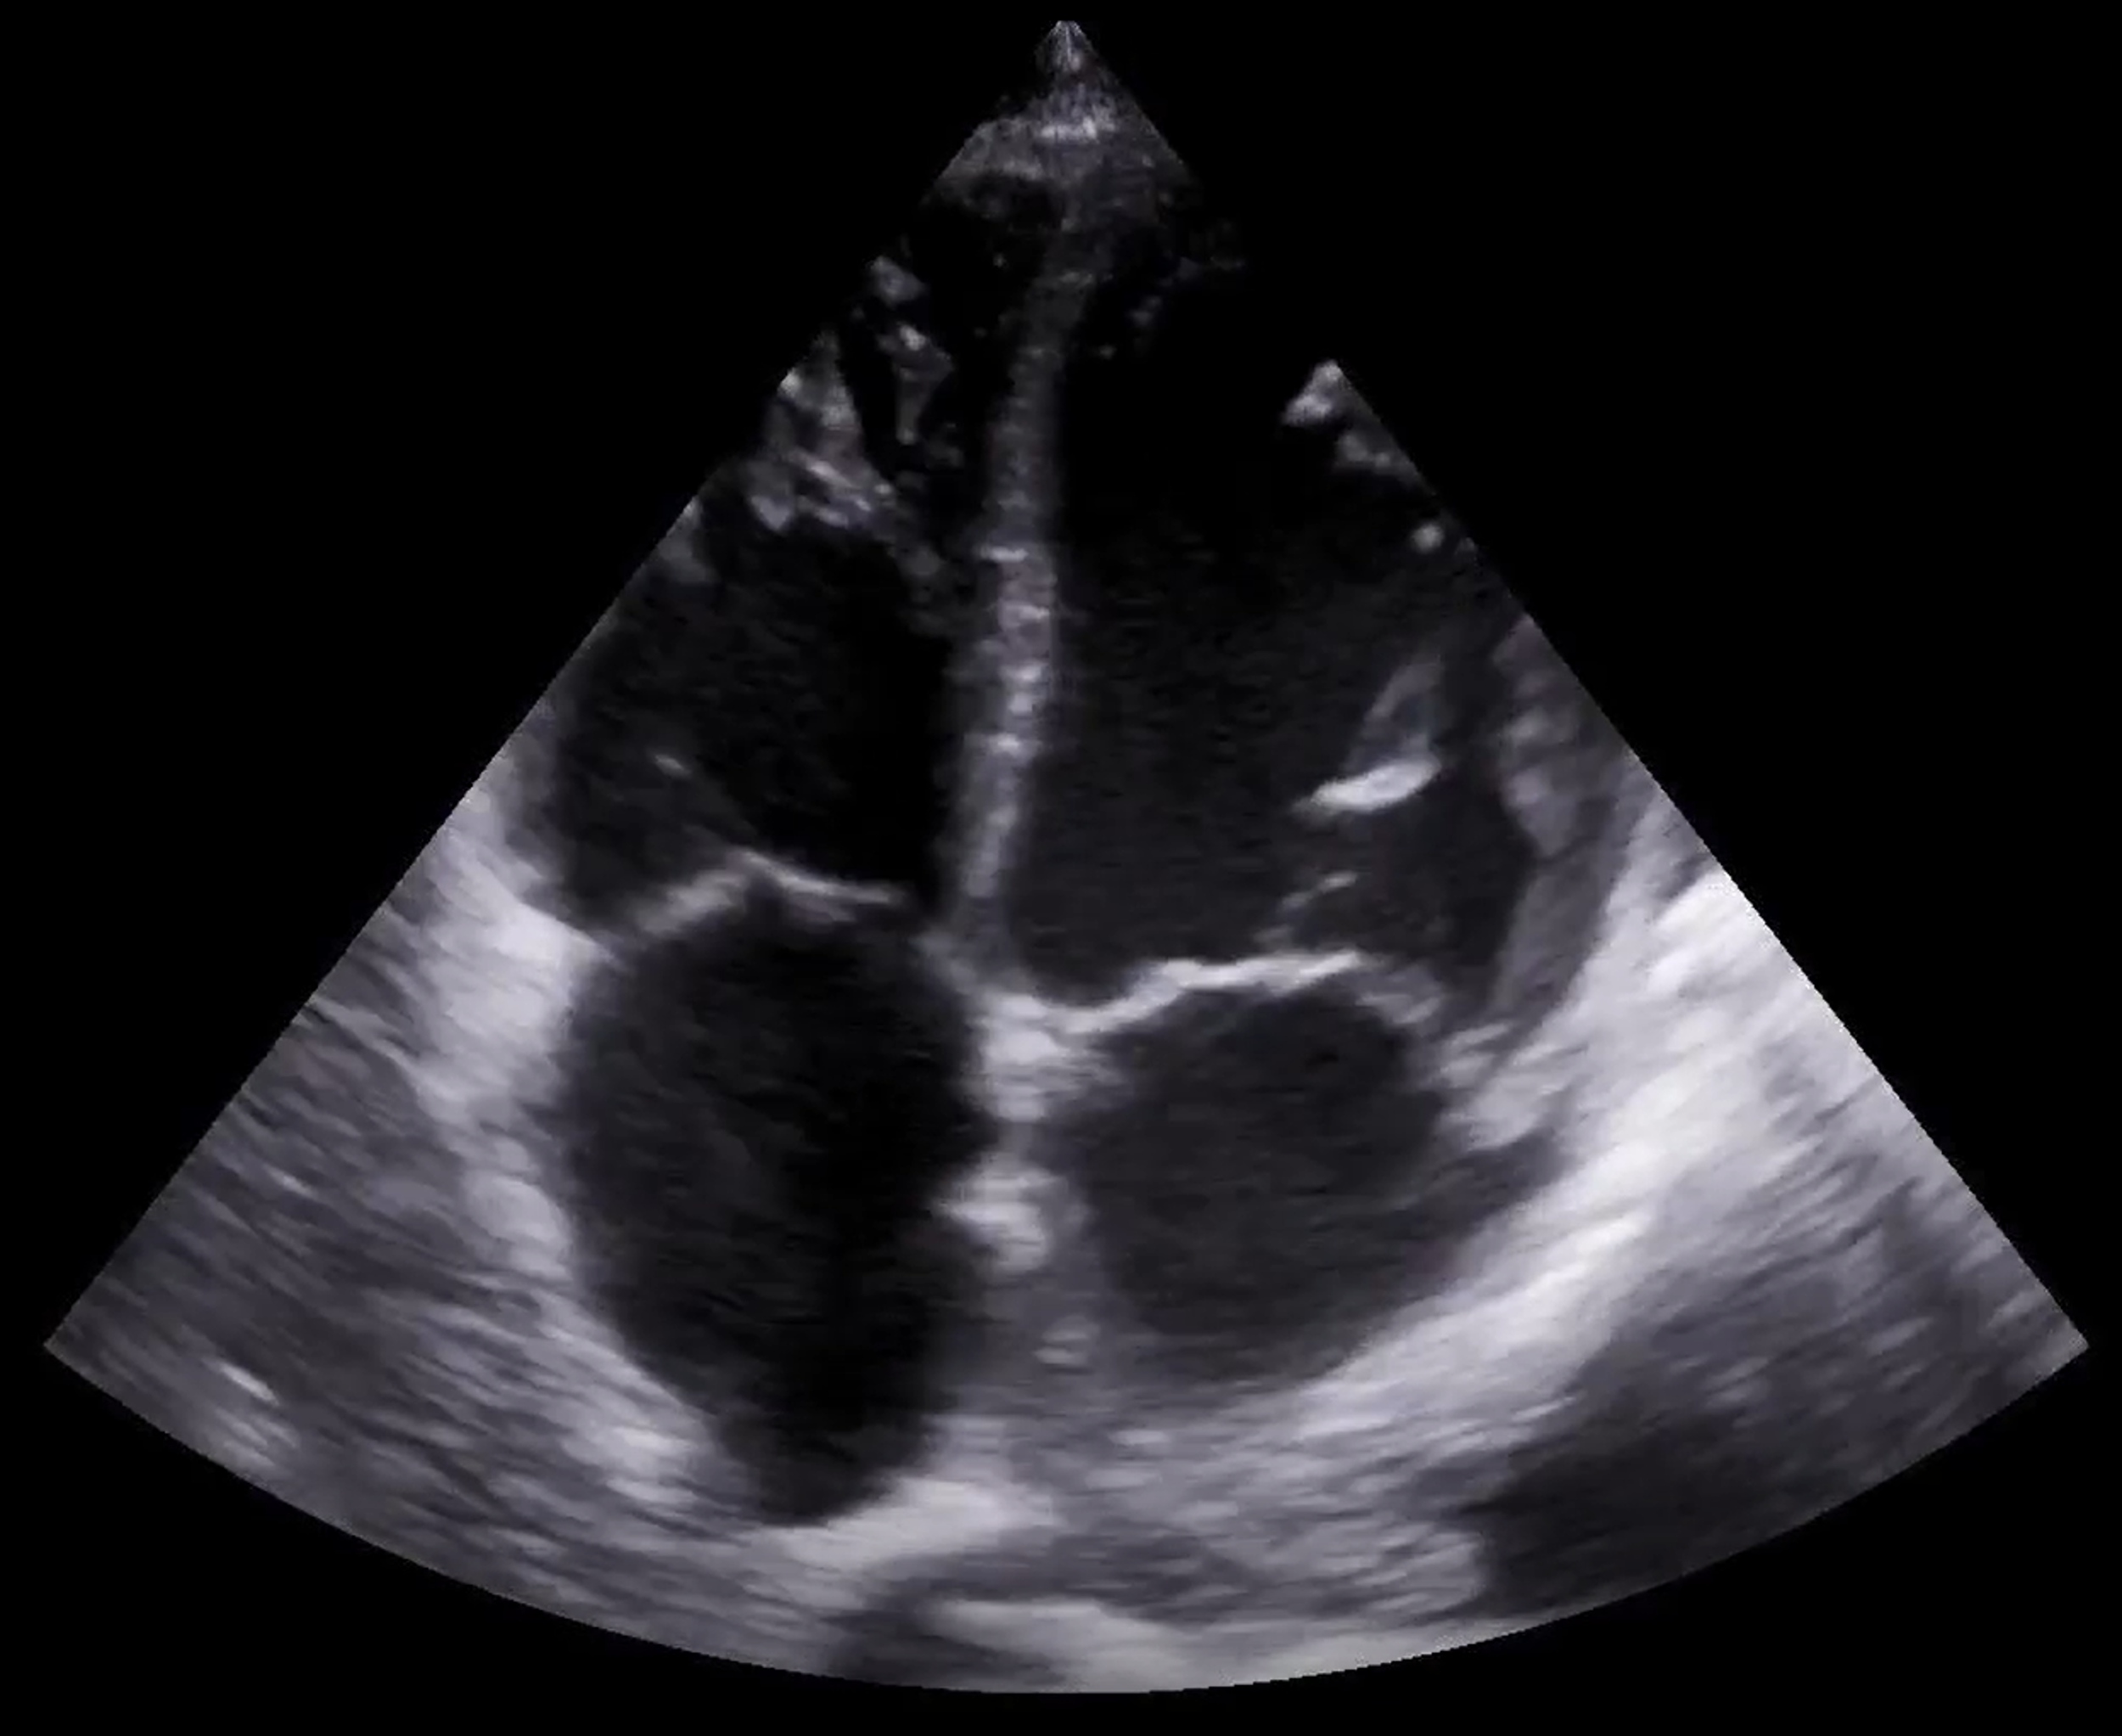

We specialize in helping medical education programs integrate Point-of-Care Ultrasound (POCUS) into their curriculum with clarity, confidence, and clinical relevance. Our team brings deep expertise in ultrasound education, curriculum development, and clinical integration—offering tailored consulting services that support both learners and faculty. Whether you're building a program from the ground up or refining an existing one, we partner with you to deliver high-quality, hands-on ultrasound training that enhances patient care.

- Guest Instruction for Students – Hands-on POCUS teaching tailored to your learners.

- Image Review – Expert evaluation of learner scans with constructive feedback.